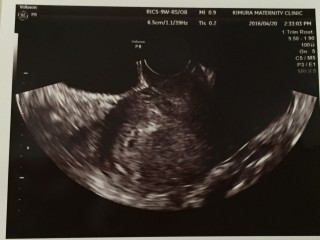

双子ちゃんです。 それぞれ7.3㎜、7.0㎜です。 しっかり元気に育ってくれることを願うばかり(^人^)